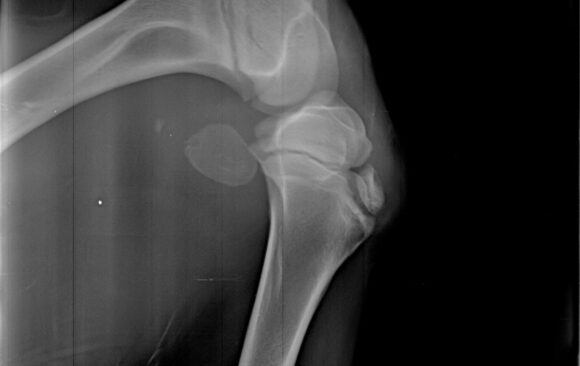

Dan za pregled

Malena Stana je mirna i puna poverenja ležala tokom pregleda, puštajući da je namestimo kako je za snimanje rendgenom bilo...